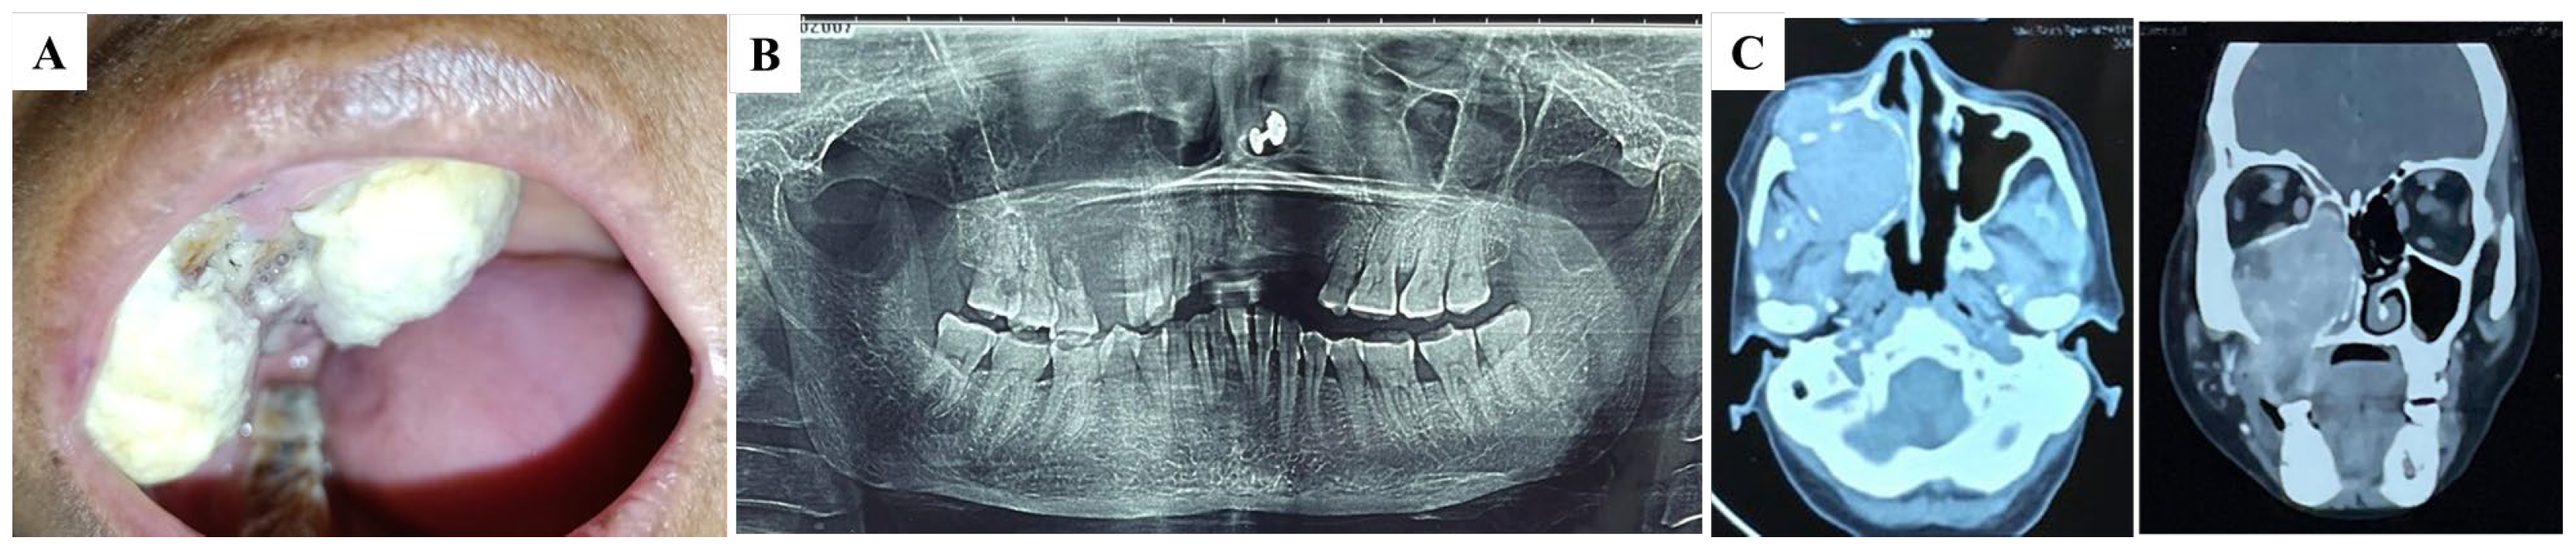

2. Detailed Case Description

| Habiba et al. (present study) | Buccal and palatal mucosa | F | 50 | Yes | Lung, adrenal gland, bone |